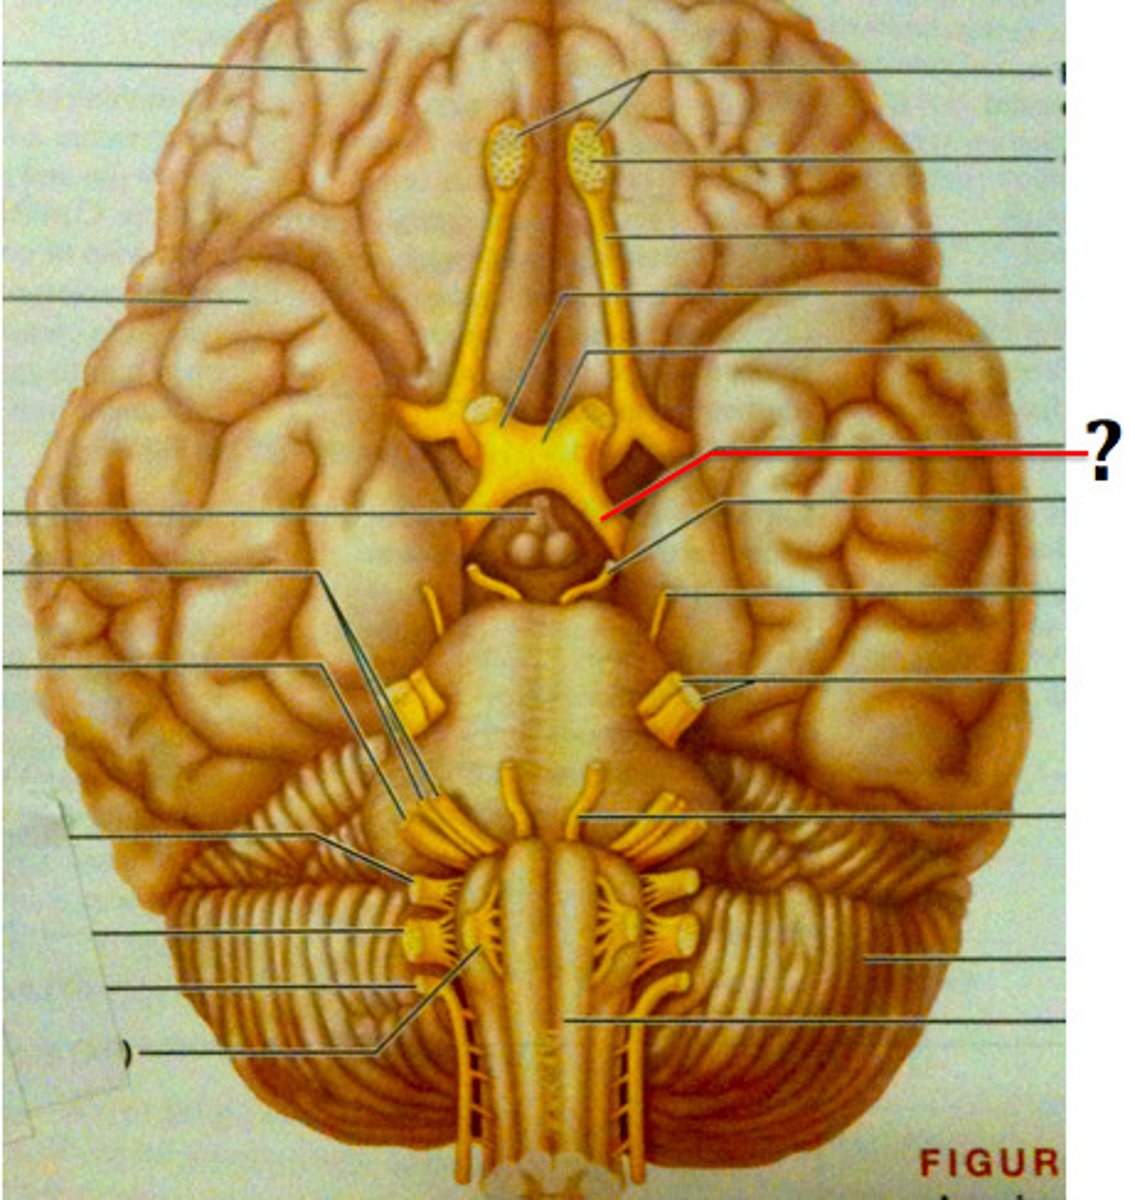

branches of olfactory nerve (cranial nerve I)

double check this

olfactory bulbs

olfactory tracts

double check this

optic nerves (cranial nerve II)

optic chiasma

optic tracts

CNIV (trochlear nerve)

CNVI (abducens nerve)

CNIII (oculomotor nerve)

CNVIII (vestibulocochlear) (acoustic nerve)

CNX (vagus nerve)